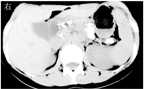

CP典型的CT表现为胰腺钙化、胰管扩张、胰腺萎缩,其诊断的灵敏度和特异度分别为80%、90%以上[24]。CT检查是显示胰腺钙化的最优方法(图2),CT平扫检查可显示胰腺微小钙化灶。常规MRI检查对CP的诊断价值与CT相似,对胰腺实质改变检查敏感,但对钙化和结石的显示不如CT。MRCP主要用于检查胆、胰管的病变,如主胰管扩张、胰腺先天变异、胆管扩张或狭窄等(图3)。